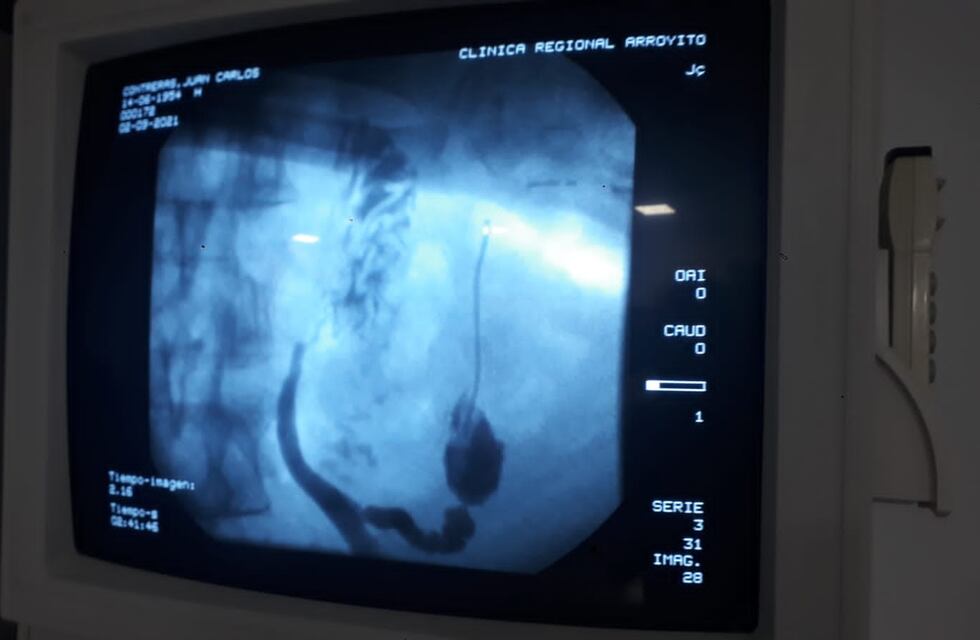

Días atrás la medicina de Arroyito y la Clínica Regional volvieron a dar un paso más hacia la excelencia medica luego de realizar por primera vez en nuestra ciudad y marcando un punto histórico, una colangiopancreatografía retrógrada endoscópica en la Sala de Hemodinamia de la institución.

El procedimiento combina la endoscopia gastrointestinal de la parte superior del aparato digestivo y radiografías para tratar los problemas de los conductos biliares y pancreáticos. Es un procedimiento de cirugía endoscópica realizado en los grandes centros urbanos por especialistas con mucho entrenamiento en técnicas endoscópicas.